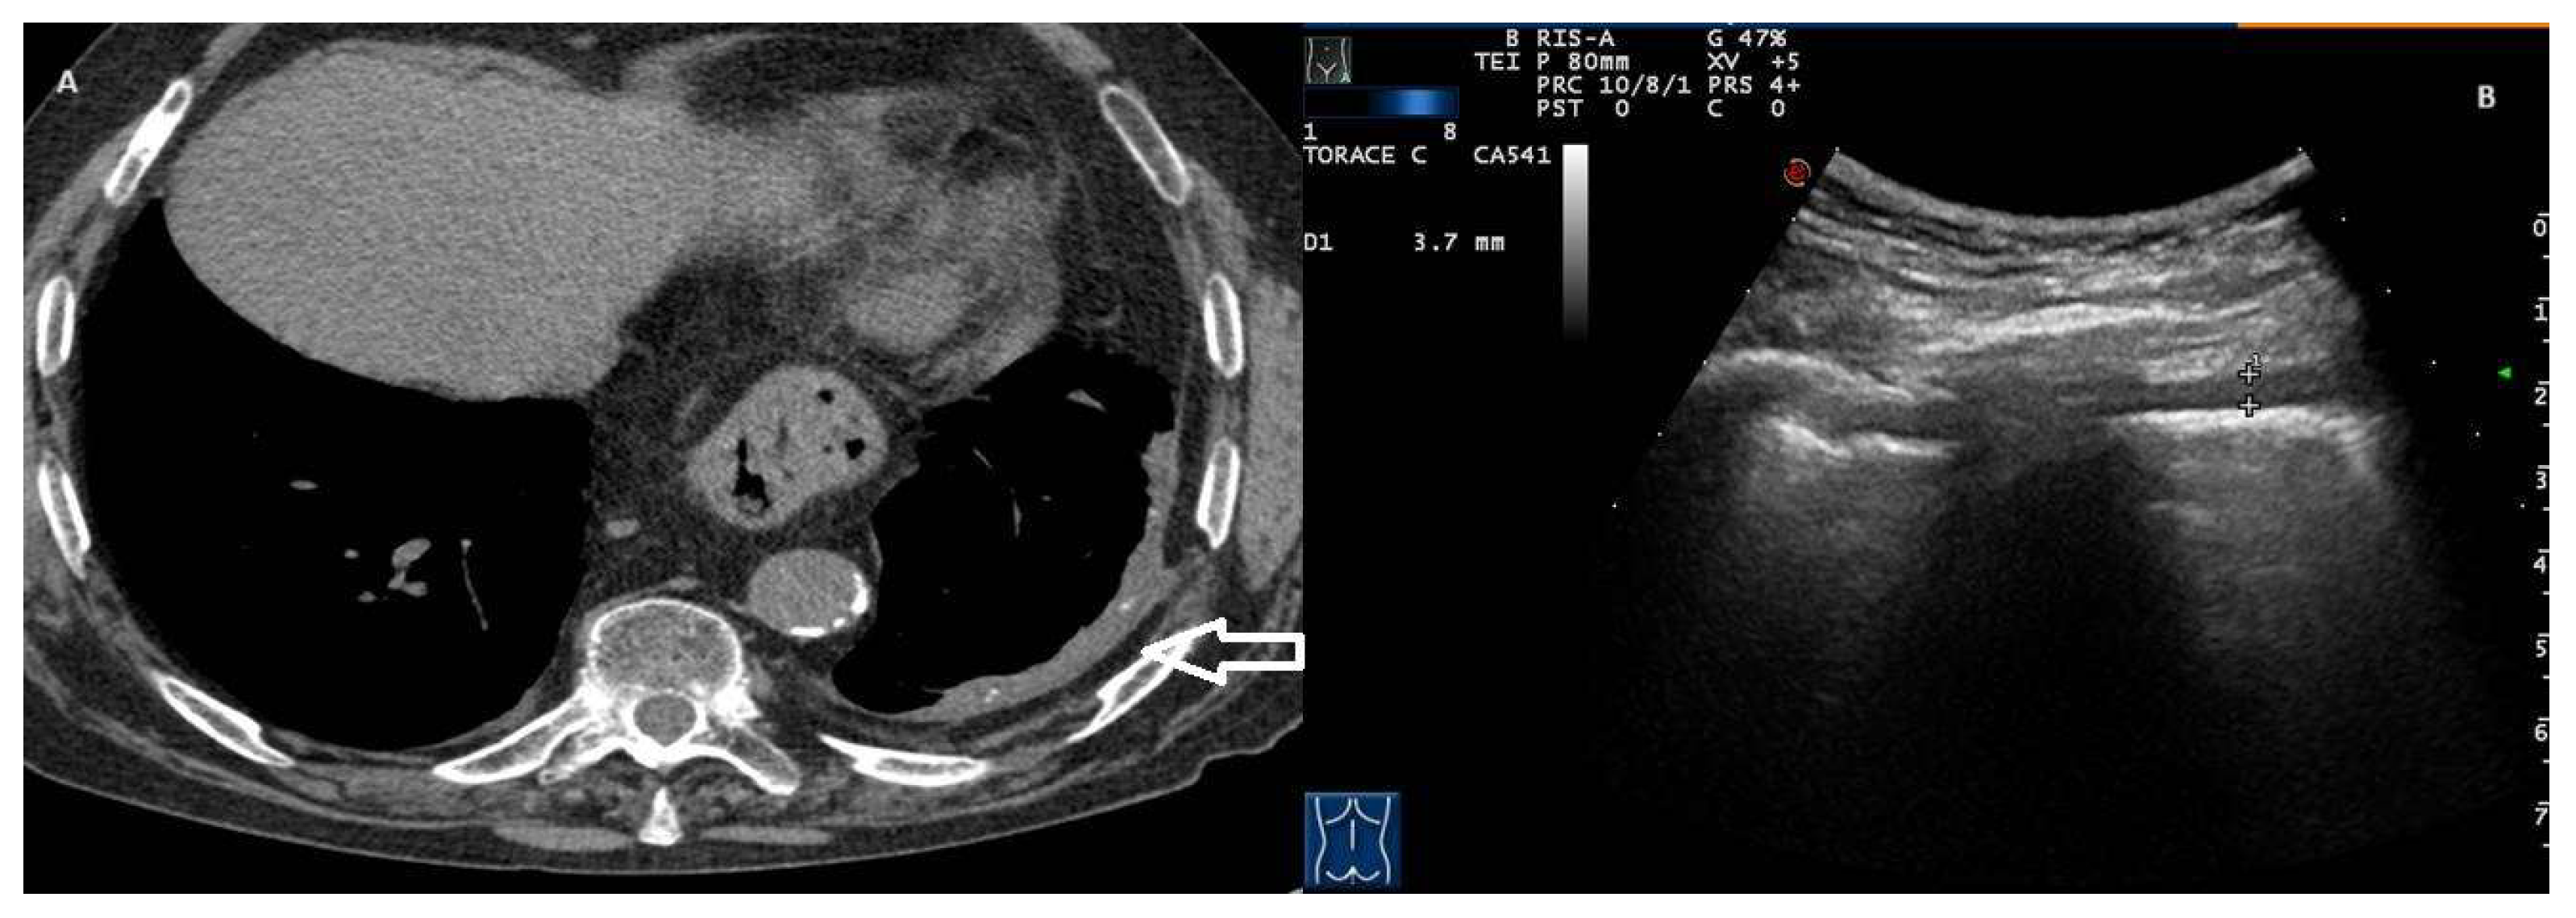

In our study, a thickened pleural line was observed in 7 out of 83 true cases of PNX (8.4%). A thickened pleural line associated with an attenuated or absent sliding sign represents a TUS finding associated with fibrothorax, a chronic sequela consisting of severe scarring and fusion of the pleural layers surrounding the lungs, leading to decreased movement of the lung and rib cage [9]. Although the thickening of the pleural line is very marked in fibrothorax cases, a thickened pleural line can also be observed in PNX, especially if it occurs in patients with adhesion phenomena and chronic pulmonary comorbidities (Figure 3, Video S2).

Figure 3. (A) Axial CT image with soft tissue window documents left, pleural thickening with calcifications and expansion of extrapleural fat (arrow); these features are suggestive of benign pleural fibrosis. Note the presence of a hiatal hernia. (B) Transthoracic ultrasound scan with a convex probe (7 MHz) corresponding to pleural fibrosis in the CT image, which shows an irregular hypoechogenic pleural thickening (3.7–5 mm). Videoclip 2 also shows the absence of a gliding sign with the presence of a “lung point”.